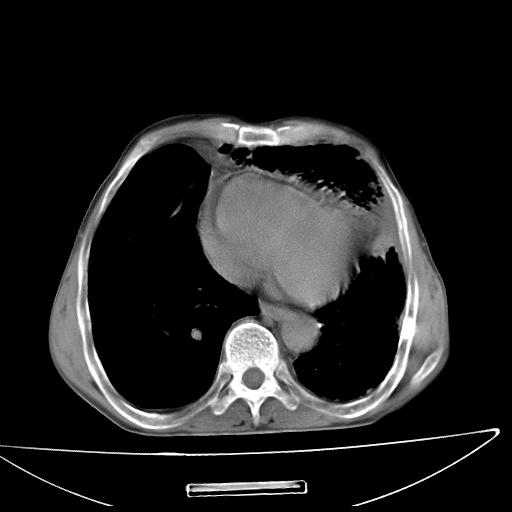

男  70岁,发烧咳嗽4天。盗汗,消瘦。无痰中带血丝,以前有肺tb病史,ct见,双肺tb,左侧胸廓塌陷,左胸膜肥厚粘连。纵隔移位,右侧胸腔积液,大家说说那个心影前左肺舌叶除了肺大炮还有炎症还是干酪性肺炎?有占位吗?我看纵隔淋巴结也大。

是胃,纵膈未见明显肿大淋巴结。

1)两肺继发性肺结核并左肺上叶肺不张,支气管扩张。2)双侧胸膜炎(胸膜增厚+少量胸腔积液)。